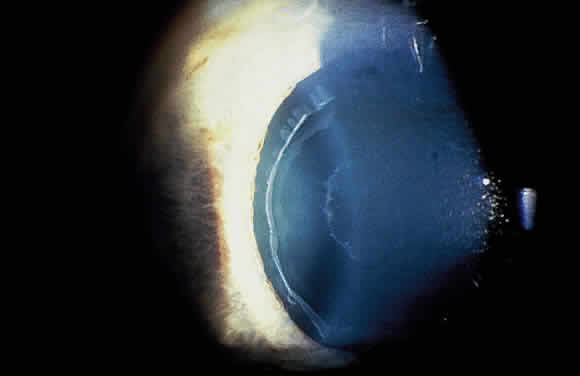

Campbell describes concavity of the midperipheral iris in patients with pigmentary glaucoma and hypothesizes that pigment dispersion may be caused by anterior packets of zonules rubbing against the peripheral iris in the large myopic eyes.189 This theory is supported by histopathologic findings,189 by photogrammetric studies of anterior chamber dimensions,206 and by ultrasound biomicroscopic study.207,208 Photogrammetric studies of eyes with PDS have shown deeper anterior chambers, particularly in the midperiphery, than could be attributed to age, sex, or refractive error. Posterior bowing of the iris with iridozonular contact has been demonstrated on anterior segment ultrasound biomicroscopic examination of patients with pigmentary dispersion or pigmentary glaucoma (Fig. 18A).

Fig. 18. Ultrasound biomicroscopic image of concave iris in a patient with pigment dispersion syndrome. A. Notice the concave iris and iris contact with lens/zonules. B. Image of same eye after laser iridotomy with resolution of iris concavity and diminished iridolenticular contact. (Courtesy Dr. Robert Ritch)

A “reverse pupillary block” has been proposed as the explanation for this posterior bowing.207–209 In 1991, Campbell reported flattening of the iris and reflux of pigment into the posterior chamber when he performed laser peripheral iridotomies in 10 eyes of seven patients with pigmentary dispersion.210 Others have made similar observations,207–209 and have also described flattening of the iris with miotic therapy208 and with reduced blinking.211 It is postulated that a pressure gradient between the anterior and posterior chambers develops when aqueous is forced into the anterior chamber (perhaps by ocular movement) and cannot flow back into the posterior chamber because of a one-way valve effect at the junction of the pupillary iris and lens. This pressure gradient then pushes the iris posteriorly. Not all patients with PDS demonstrate iris flattening after laser peripheral iridotomy,212 and in one case report, laser iridotomy did not eliminate exercise-induced pigment dispersion.213 These studies suggest that other factors also may play a role in this disorder.